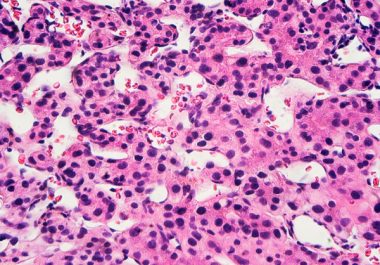

The FDA approved a combination of an immunotherapy and a therapeutic that can stop tumors from growing blood vessels for certain patients with liver cancer.

The FDA approved using a combination of nivolumab and ipilimumab, two immune checkpoint inhibitors, to treat certain patients with hepatocellular carcinoma.

The FDA expanded the use of the immunotherapy pembrolizumab to include the treatment of certain patients with liver cancer.